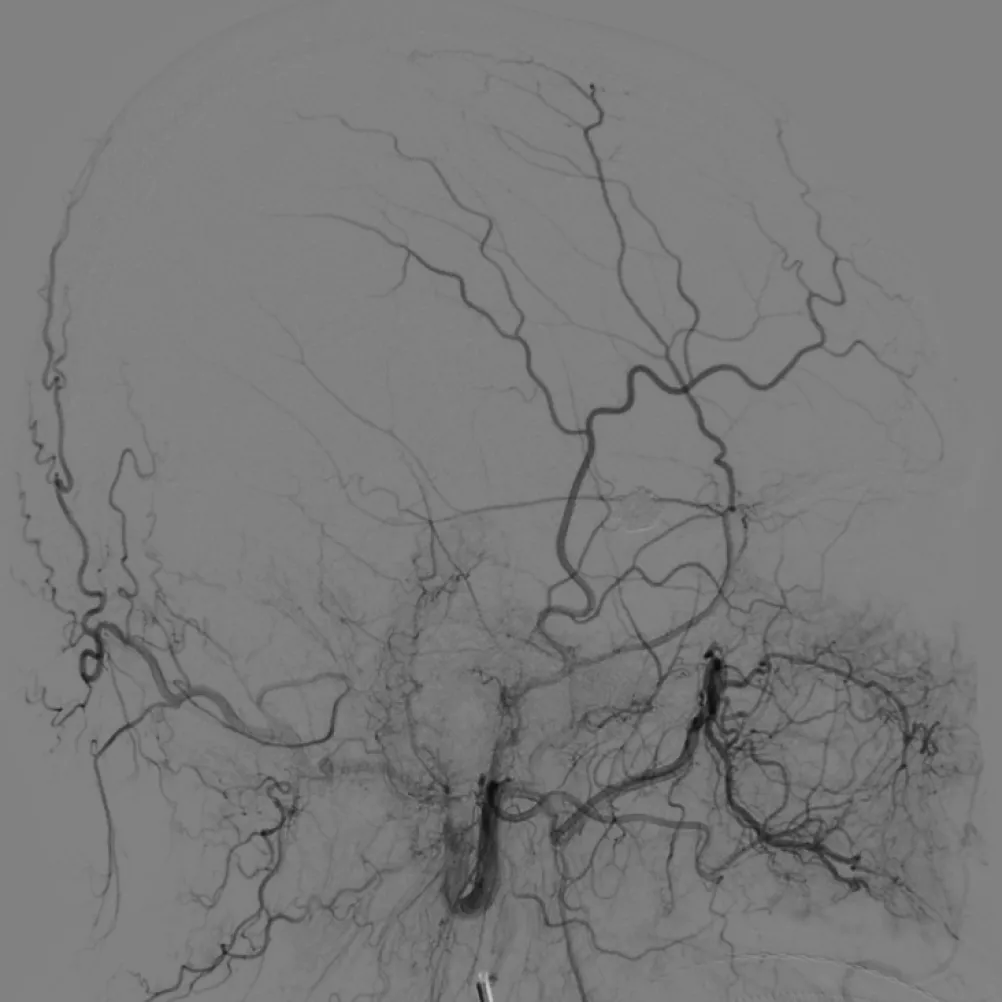

拔管后造影:

SONIC微导管头端解脱,右侧眼动脉显影良好,未见拔管牵拉痉挛表现

可见SONIC微导管可解脱头端显影

术后即刻,供血分支、瘘口区及引流静脉完全消失,不显影。